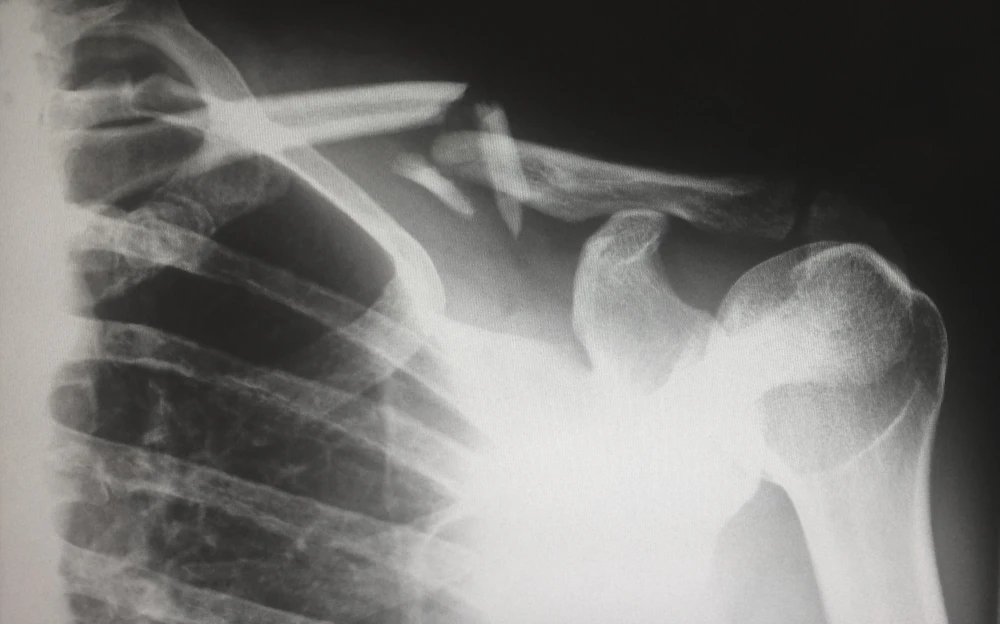

The shoulder joint is a structure made up of three bones—the clavicle (collarbone), the scapula (shoulder blade), and the head of the humerus or upper arm. These three bones come together to form the capsule that the head of your upper arm sits in. This design grants you more mobility than any other joint in your body—you can swing your arm up overhead, behind you, and side-to-side.

The price of that range of motion, however, is a lack of stability. The ball of the humerus is held in place only by your rotator cuff—a group of four small muscles—and the labrum—padding of cartilage that aids in stability. Every time I throw a punch or elbow or parry a jab, I’m stressing the rotator cuff muscles and wearing down the labrum. Eventually, they just gave out.